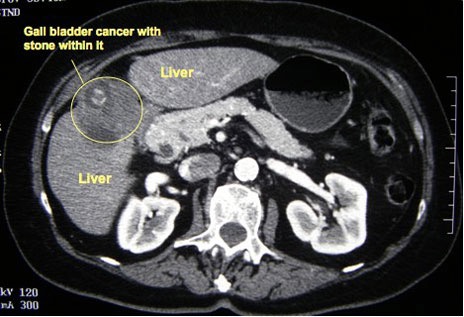

CT scan gall bladder

CT scan picture showing a cancer that has arisen from the gall bladder. A gallstone can also be seen

Spiral CT scan probably gives the best estimate of the extent of disease. However, MRI scanning gives equally high-resolution images, with the additional benefit of providing an MRCP. CT and MR usually give adequate information about the localblood vessels, and hepatic angiography is rarely indicated.